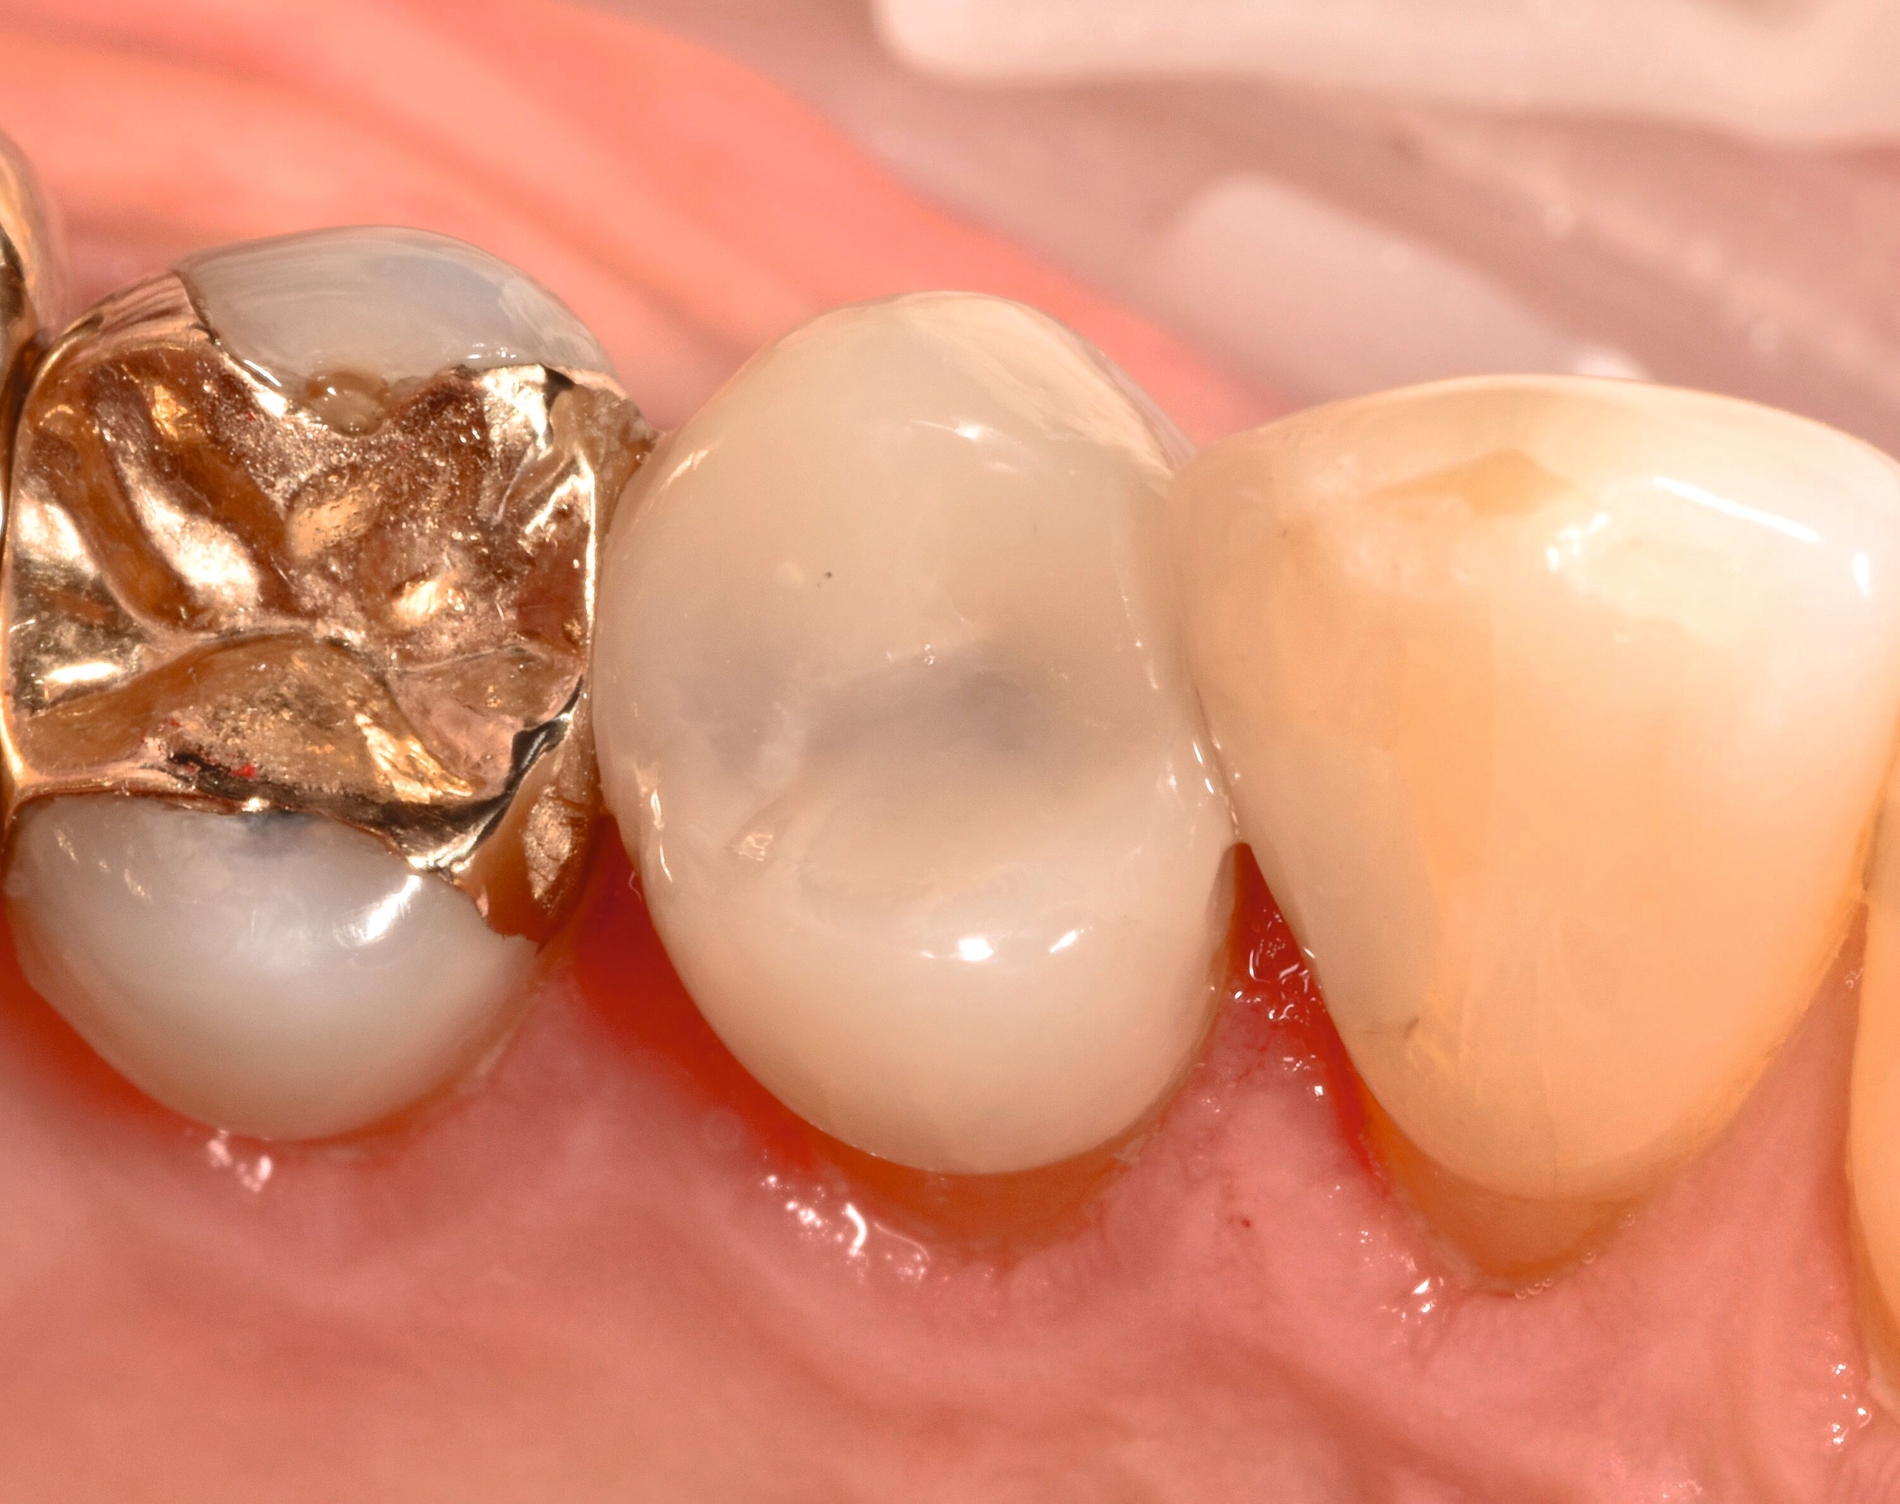

... mit Höckerersatz im Seitenzahnbereich

Für die Höckerüberkappung bedarf es eines ausreichend stabilen und abrasionsfesten Materials, das durch okklusale Kräfte belastet werden kann und die anatomische und funktionelle Rekonstruktion des Zahnes ermöglicht. Die Evidenz zur Verwendung von Kompositmaterialien bei Seitenzahnkavitäten mit Höckerersatz zeigt in mehreren Studien gute Überlebensraten [Deliperi et al., 2006; ElAziz et al., 2020; Fennis et al., 2014]. Van Nieuwenhuysen et al. [2003]berichtetenvon hohen Versagensraten sowohl bei Komposit- als auch bei Amalgamrestaurationen (30,4 Prozent beziehungsweise 28,1 Prozent). Diese Daten sind jedoch aufgrund der Verwendung älterer Kompositmaterialien als veraltet zu werten.

MERKE: Moderne Kompositmaterialien sind leistungsfähig und entsprechen den Prinzipien der minimalinvasiven Zahnmedizin. Insofern ist die Höckerrestauration mittels Komposit möglich (Abbildung 2).

Die Gruppe hat mit starkem Konsens die Empfehlung ausgesprochen, dass für Höcker-ersetzende Restaurationen insbesondere bei spezifischen Einflussfaktoren auf Zahn-, Mund- und Patientenebene (zum Beispiel eingeschränkte Compliance, schlechte Zugänglichkeit, komplexe funktionelle Rehabilitation) der Einsatz von indirekten Kompositrestaurationen erwogen werden kann.